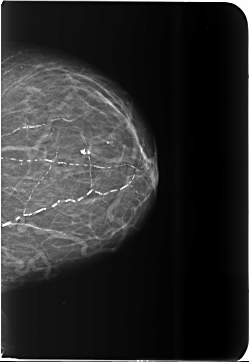

B_3481_1.RIGHT_CC

LEFT_CC LINES 5784 PIXELS_PER_LINE 3984 BITS_PER_PIXEL 12 RESOLUTION 50 NON_OVERLAY